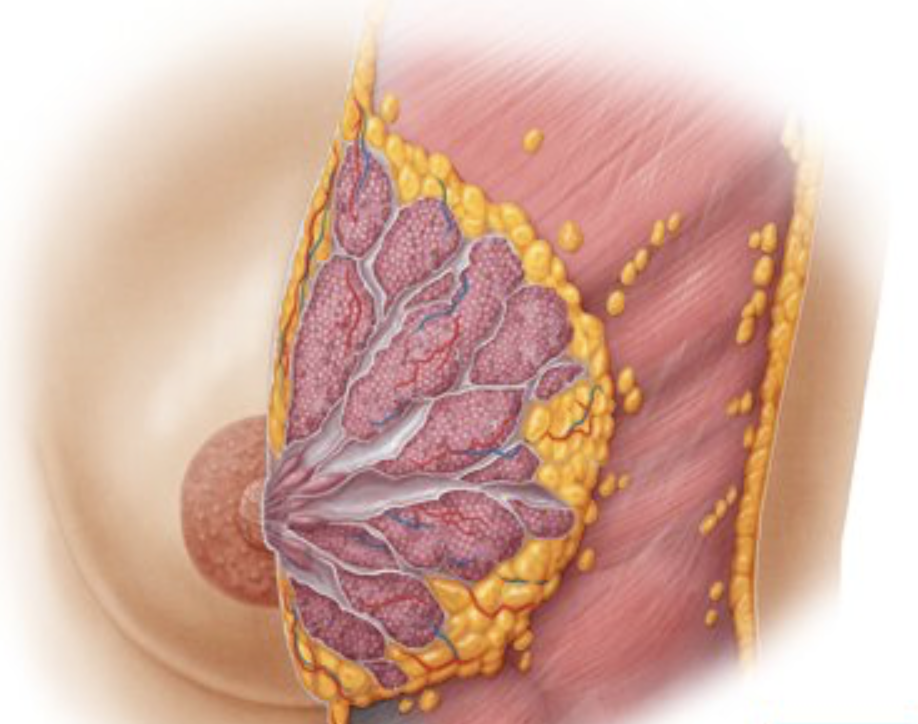

No eixo vertical, a mama se localiza entre os ____ e ______ EIC. No eixo horizontal, ela vai da linha axilar _______ (anterior/médio/posterior) até a região _____________.

No eixo vertical, a mama se localiza entre os 2o e 5o/6o EIC. No eixo horizontal, ela vai da linha axilar anterior até a região paraesternal.

A mama é composta por ácinos glandulares que, pelos ductos lactíferos, convergem em seios lactíferos que desembocam na papila.

Verdadeiro.

Entre a fáscia da parede anterior do tórax e a glândula mamária encontra-se ______________________.

Entre a fáscia da parede anterior do tórax e a glândula mamária encontra-se tecido conjuntivo retromamário.

Qual é o quadrante com a maior quantidade de tecido mamário?

Superior-lateral.

Também há um prolongamento desse quadrante, chamado de prolongamento de Langer (ou cauda axilar de Langer).

A vascularização da mama é feita por pedículos. Descreva os vasos envolvidos em cada um deles: